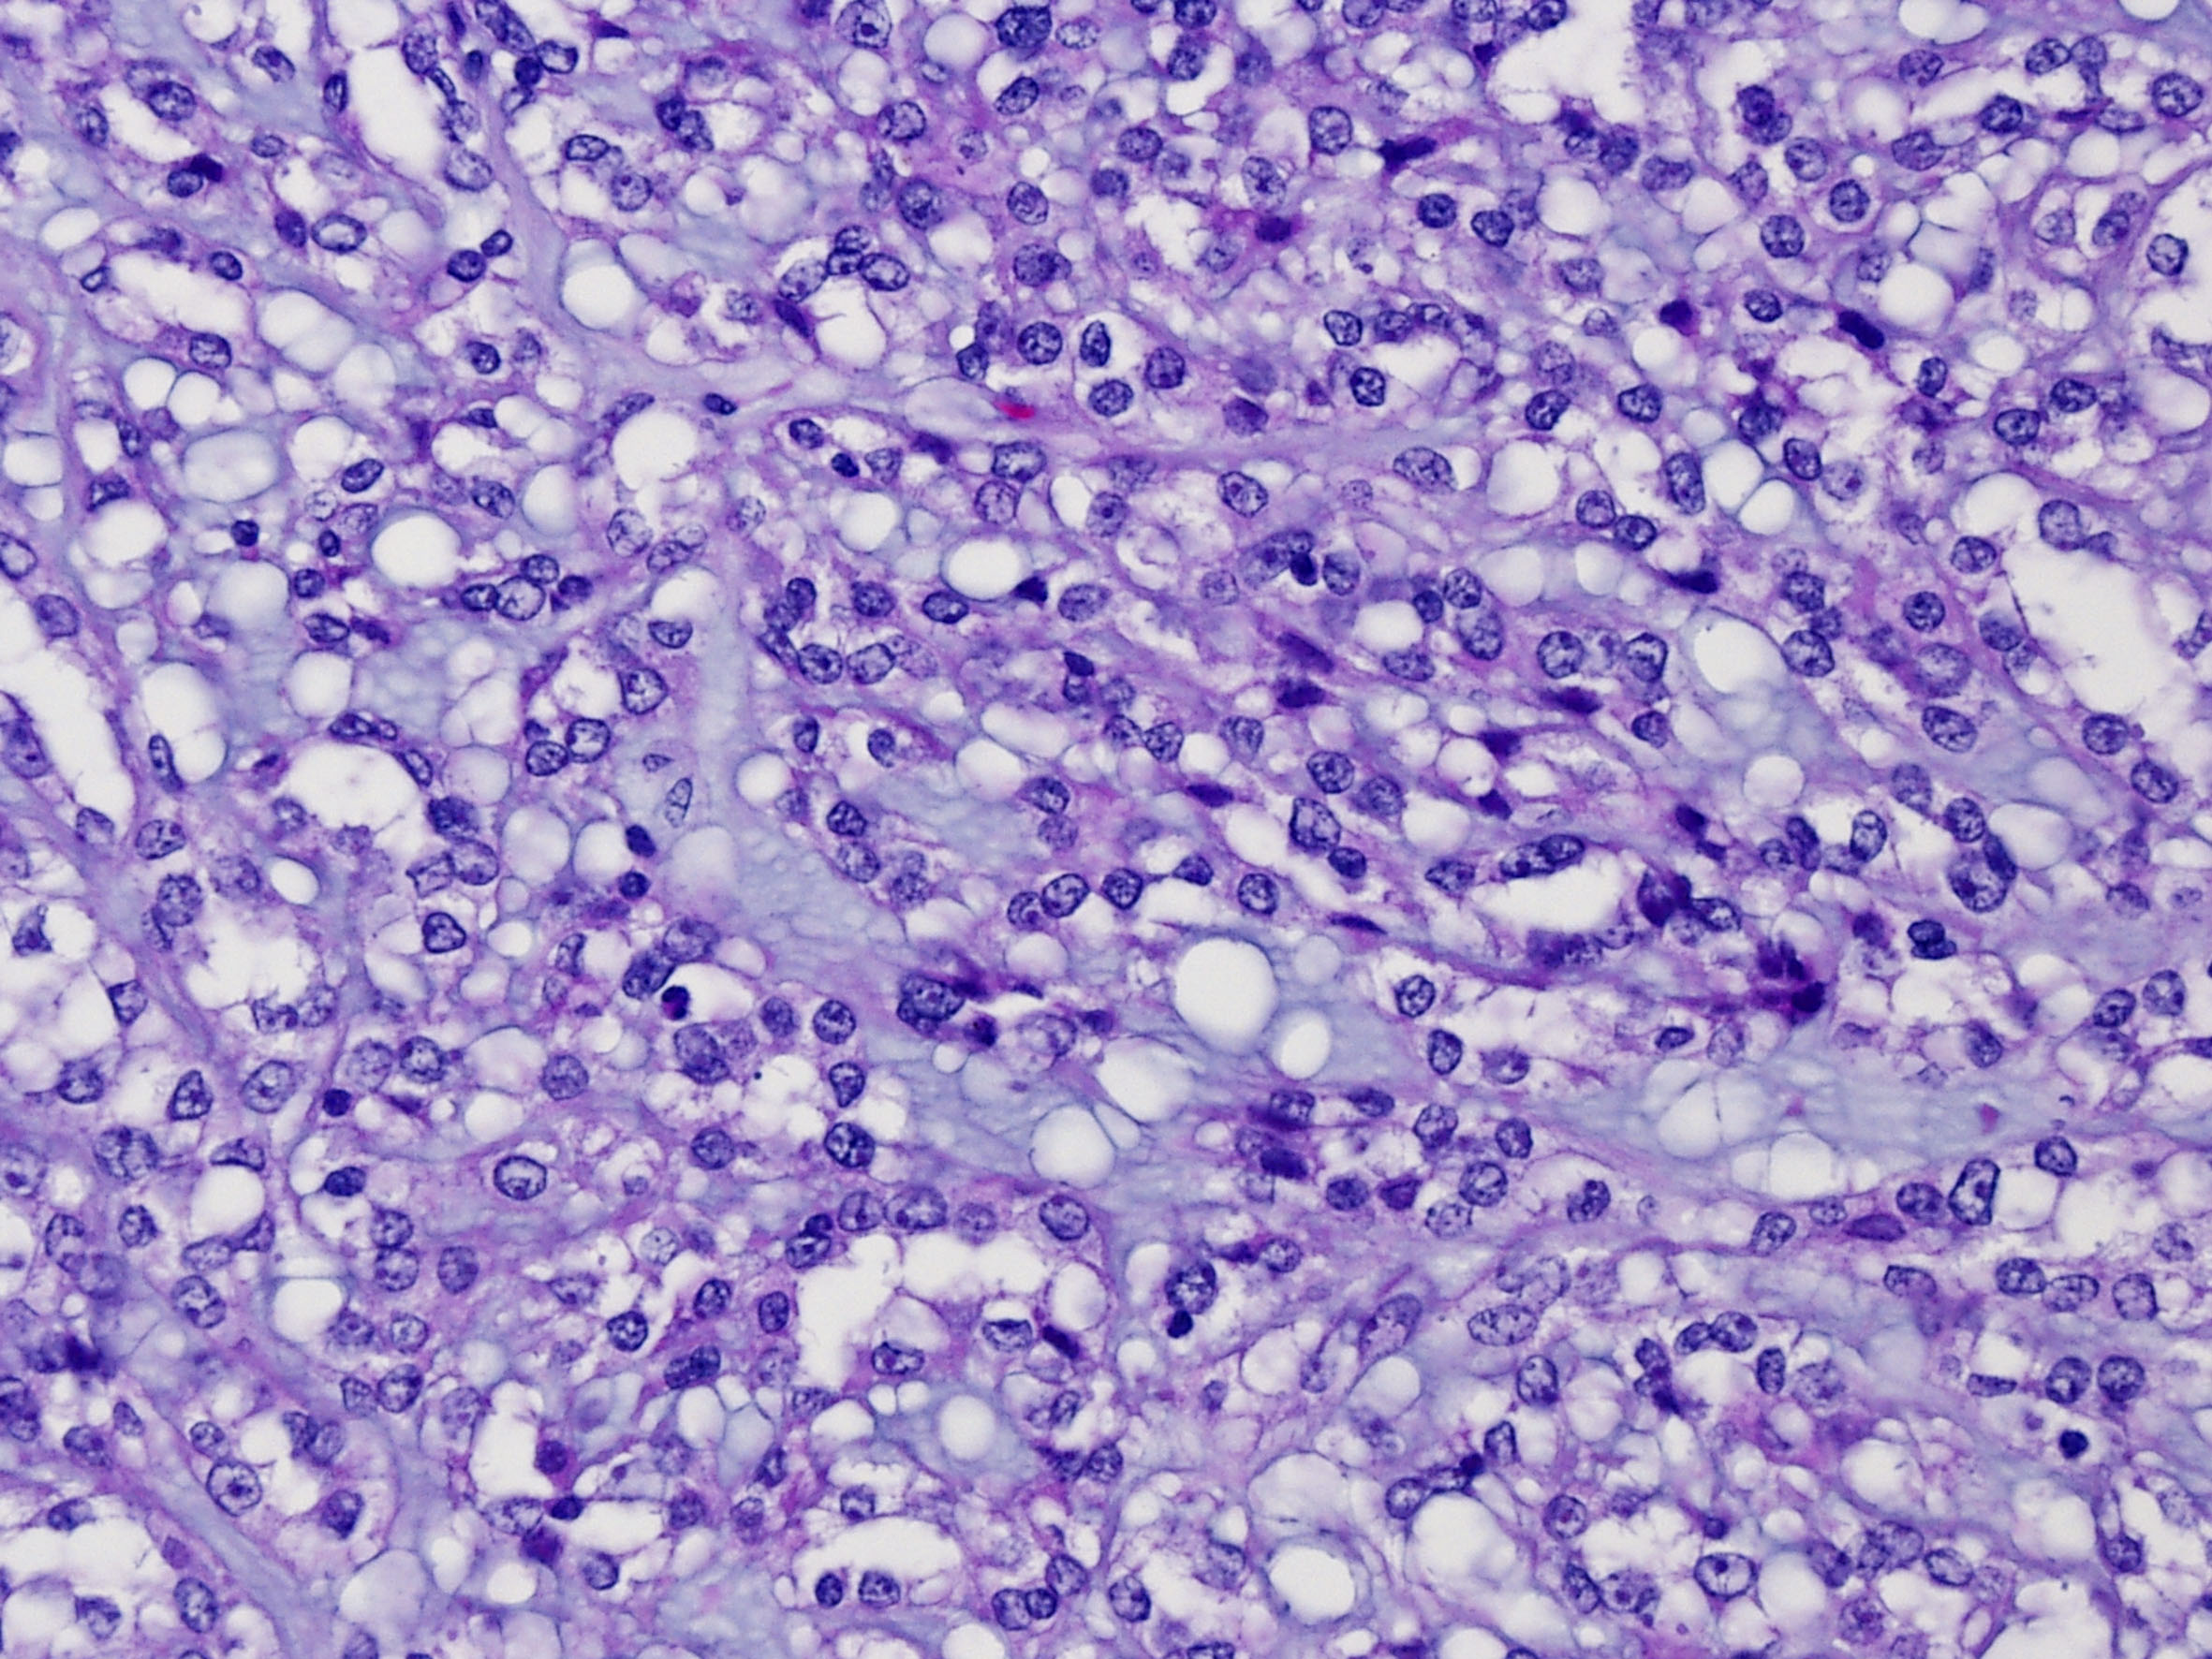

Classification of renal tumors

Case ID: 47